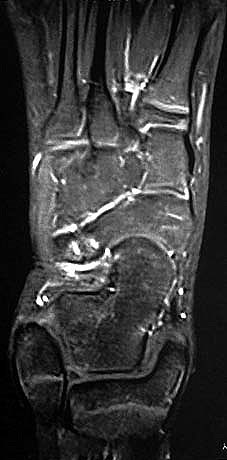

MRT und CT konkurrieren in der Fein-Darstellung der Knochenbrücke, der Beurteilung der nichtbetroffenen Anteile des Subtalargelenkes und der Sekundärveränderungen. Das MRT bietet den Vorzug, bindegewebige und knorpelige Strukturen (Abb. 2) und bei Einsatz von Kontrastmittel auch knöcherne Aktivierungsphänomene genau abzubilden; die knöcherne Feinstruktur und genaue Ausdehnung dagegen ist mit dem Dünnschicht-CT wesentlich exakter darstellbar (Abb.3). In manchen Fällen ist eine 3-D-Rekonstruktion des CT hilfreich. Besonders wichtig ist eine geeignete Schichtebenen-Wahl:

Die zweite wichtige Form tarsaler Coalitiones findet sich im medialen Bereich des Subtalargelenkes, am häufigsten unter Einbeziehung der medialen, mittleren Facette des talocalcanearen Gelenkes (Abb. 9). Die Ausdehnung der zunächst fibrösen, später zunehmend verknöcherten Brückenbildung kann sehr unterschiedlich Anteile der hinteren Kammer des unteren Sprunggelenkes mitumfassen; auch rein dorsomediale Formen ohne Einbeziehung der medialen Facette werden beobachtet (Abb. 2) 67 (Hamel 2008).

Diagnostisch sollte neben Röntgenübersichtsaufnahmen (indirekte radiologische Zeichen: Dorsaler Traktions-Osteophyt am Taluskopf, „talar beaking“; kontinuierliche Linie der Trochlea-tali-Kontur übergehend in die Sustentaculum-tali-Kontur, „C-Zeichen“ (Abb. 11) 10) immer die dreidimensionale Bildgebung eingesetzt werden. Das MRT (mit Kontrastmittel) kann die Struktur der Brückenbildung und z.B. die Qualität des Restgelenkes (Knorpel-Dicke) besonders gut abbilden; das Dünnschicht-CT zeigt die knöcherne Feinstruktur im Bereich der Coalitio und den oft sehr schrägen Spalt-Verlauf im Frontalschnitt dagegen häufig genauer. Meist findet sich die Überbrückung im Bereich der medialen Facette; die Schichten sollten jedoch bis weit nach dorsal beurteilt werden, da ansonsten dorsomediale Formen übersehen werden können. Rozansky et al 7 unterschieden fünf morphologische Typen auf der Basis von 3-D-CT-Rekonstruktionen. Allerdings ist eine prognostische Zuordnung bisher nicht möglich.